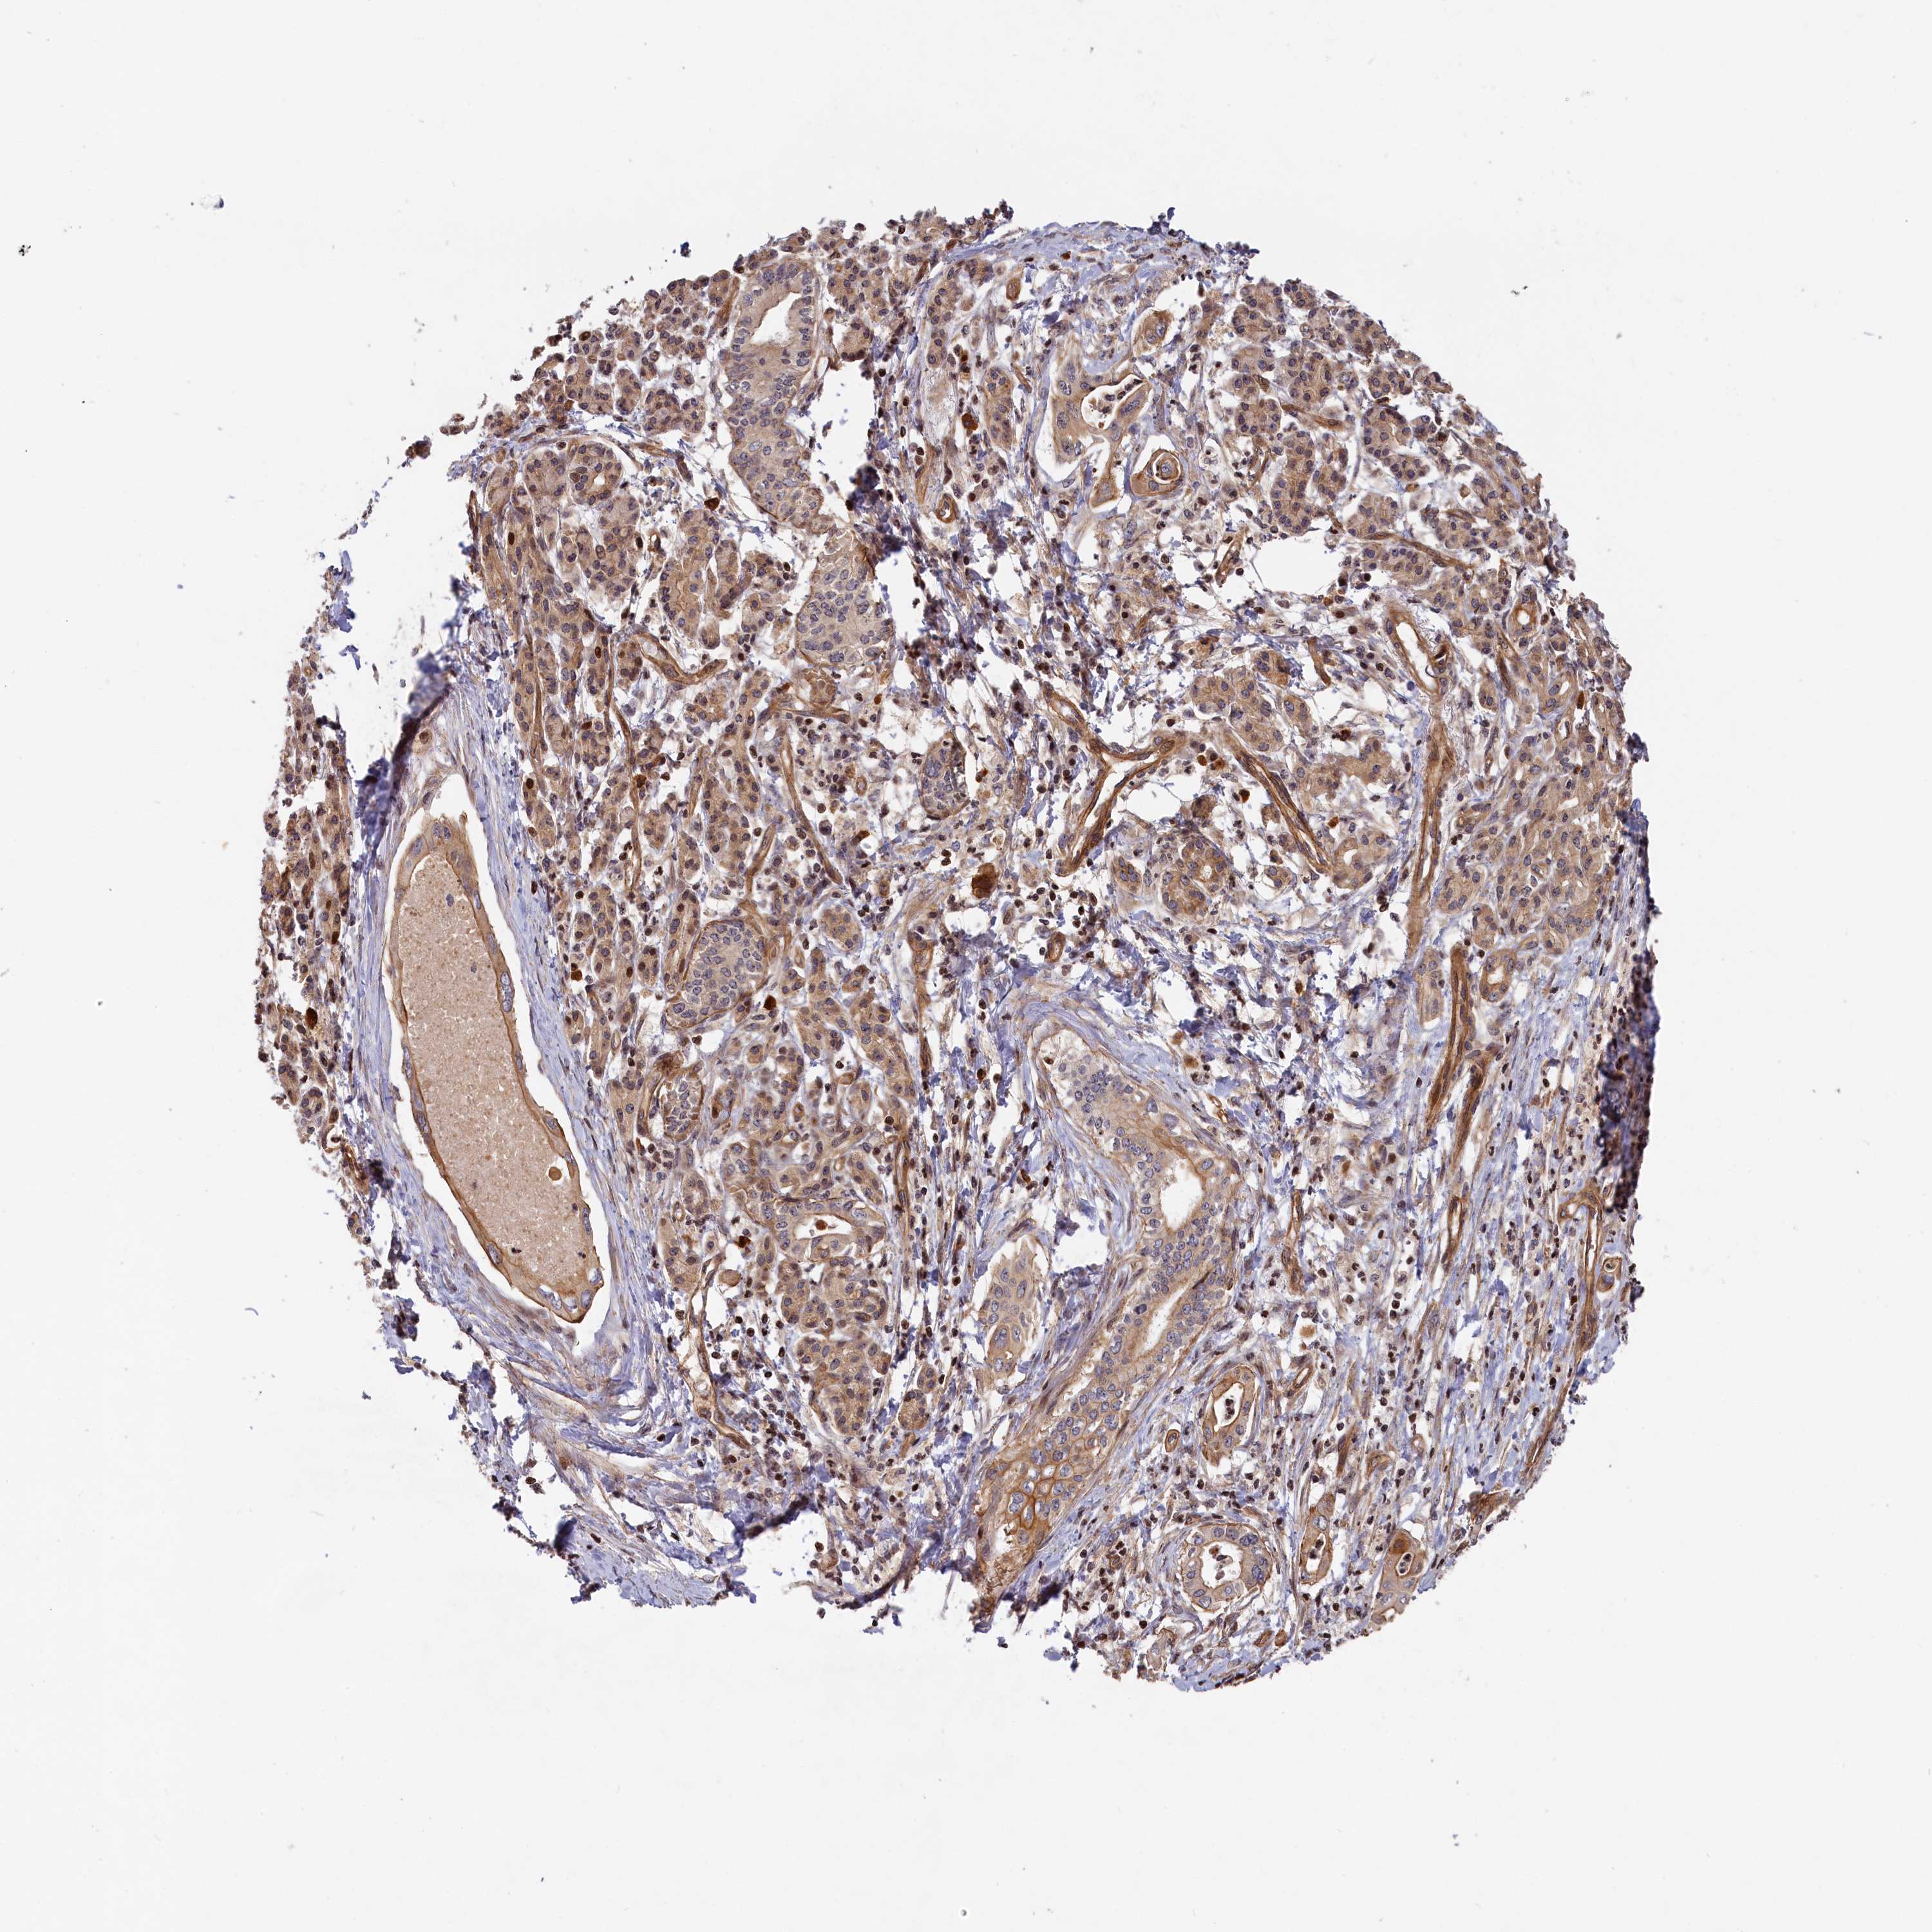

PANCREATIC CANCER - Protein expressioni

A mouse-over function shows sample information and annotation data. Click on an image to view it in a full screen mode. Samples can be filtered based on level of antibody staining by selecting one or several of the following categories: high, medium, low and not detected. The assay and annotation is described here.

Note that samples used for immunohistochemistry by the Human Protein Atlas do not correspond to samples in the TCGA dataset.

Antibody stainingi

Antibody staining in the annotated cell types in the current human tissue is reported as not detected, low, medium, or high, based on conventional immunohistochemistry profiling in selected tissues. This score is based on the combination of the staining intensity and fraction of stained cells.

Each image is clickable and will lead to virtual microscopy that enables deeper exploration of all samples and also displays staining intensity scores, fraction scores and subcellular localization as well as patient and tissue information for each sample.

Antibody HPA041515

Antibody HPA041835

Staining

High

Medium

Low

Not detected

Intensity

Strong

Moderate

Weak

Negative

Quantity

>75%

75%-25%

<25%

None

Location

Nuclear

Cytoplasmic/membranous

Cytoplasmic/membranous,nuclear

Adenocarcinoma, NOS